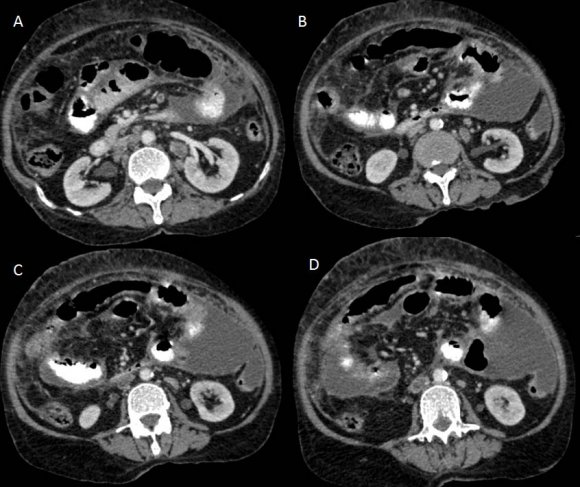

CT scan of the abdomen and pelvis (Figures: 4-8) showed changes of fatty infiltration in the liver. Multiple well-defined lymph nodes of size 1 to 2 cms were noted at portahepatis, peripancreatic region, celiac axis, left renal hilum, preaortic and para-aortic regions, precaval and paracaval regions and in right internal iliac region. Most of the lymph nodes showed peripheral enhancement with central hypodense areas of necrosis. A conglomerated matted lymph nodal mass of size 35 x 24 mm noted in the precaval region. Multiple ill-defined and nodular soft tissues infiltrate noted within the mesentery. Moderate ascites noted with mild peritoneal enhancement without septations. Ileo-caecal junction and other bowel loops appeared normal. IVC distal to renal veins showed persistent filling defect of size 10 (Anteroposterior) x 16 (Transverse) mm extending over a length of 67mm with peripheral enhancement in contrast study extending to right common iliac vein suggestive of IVC and right common iliac vein thrombosis.